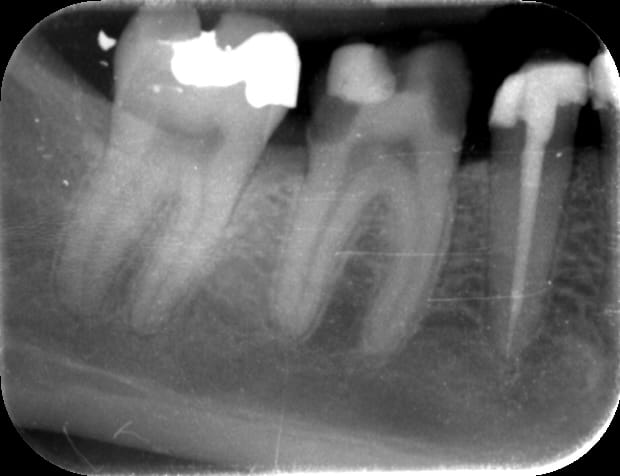

IL te restait les problemes de vitalité ( retourne jeter un oeil sur la dent au depart... )

sur lesquels on fait un pari.

sur cette RX, effectivement, la pulpe a l'air de te donner plus de marge;)

Onlay rxpréop yrf29j - Eugenol

Onlay rxp xfrksk - Eugenol